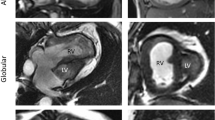

For 2D-FT MRI, the module QStrain in Medis Suite MR (version 2.1, Medis Medical Imaging Systems BV, Leiden, The Nethderlands) was used [13]. After manually setting the cine frame with smallest RV cavity area as end-systolic, the frame with largest as end-diastolic heart phase and tracing of the endo- and epicardial border in both phases, the RV was automatically divided into seven segments (Fig. 1). For each segment, peak longitudinal strain (LS, percent change in segment length from end diastole) and peak longitudinal strain rate (LSR, representing rate of myocardial deformation) were recorded (Fig. 2). The measurements were repeated twice and averaged. Global LS (GLS) and LSR (GLSR) value were calculated as the mean of all segments.

Both 2D-FT MRI and 2D-STE allow the measuring of endocardial, myocardial, and epicardial LS and LSR. In this study, we only calculated myocardial LS and LSR, since the endocardial and epicardial parameters are more affected by spatial resolution which differs substantially between the MR and echocardiographic images. In order to compare the two techniques, the segmentation had to be adapted, since the 2D-FT MRI uses seven segments while 2D-STE divides the chamber into six segments. We, therefore, joint the segments in such a way that for both imaging modalities only three segments (septal, apical, and lateral) remained. These are defined as follows in 2D-FT MRI: (septal = basal inferoseptal + mid inferoseptal + apical septal; apical = apex + apical lateral; lateral = mid anterolateral + basal anterolateral) and in 2D-STE: (septal = basal septal + mid septal; apical: apical septal + apical lateral, lateral = mid lateral + basal lateral) and shown in Fig. 1.

Regional and Global LS and LSR in BCPC and TCPC Using 2D-FT MRI

Results of the regional and global LS and LSR of both imaging modalities are shown in Table 2 and Fig. 2. In 2D-FT MRI, the LS was lower in the septal segments, while LSR did not differ between the segments. In 2D-STE, the septal segments likewise showed the lowest LS and also LSR. 28% of apical segments could not be analyzed with 2D-STE due to poor image quality.

In our cohort of HLHS patients, regional and global myocardial longitudinal deformation parameters could easily be assessed with new 2D-FT-MRI technique. Visualization was excellent in all myocardial segments and allowed measurements of LS and LSR in all patients included in this study. For septal and lateral segments, we found an acceptable agreement with LS measured by 2D-STE.